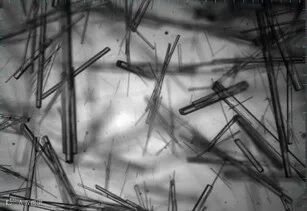

瑞舒伐他汀钙药物在结晶过程中容易形成针状晶体,细长的针状晶体容易相互堆积成网状结构,这会导致网状结构包裹溶剂、不易流动、堆密度小、抽滤困难等工艺问题。通过改变结晶工艺,可以优化结晶过程,析出的晶体以短粗的棒状为主,这大大改变了结晶体系的流动性,增大了晶体的堆密度,使得结晶工艺过程可以顺利进行。

PCM结晶监测系统可以很好地表征不同工艺条件下形成的晶体形貌,可以大幅提高结晶过程工艺优化效率。可以实时监控晶体成核、生长过程,对于结晶机理及各种影响因素的判断准确直观。同时PCM可以给出晶体形貌的数据信息,例如晶体径长比、晶体生长速率等。从晶体径长比数据也可以看出,工艺改变后,晶体的径长比数值增大,说明晶体变短,变粗,这与PCM晶体图像结论相符。